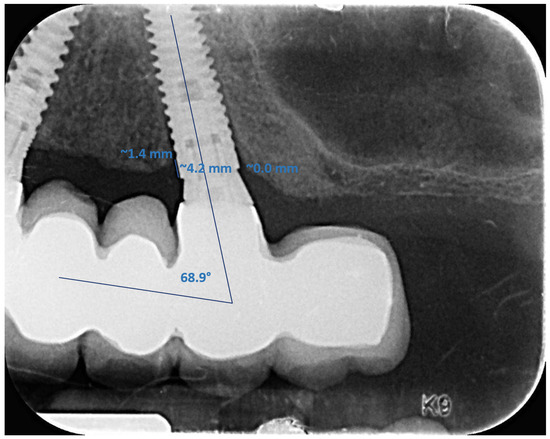

2.4.4. Radiographic Measurements